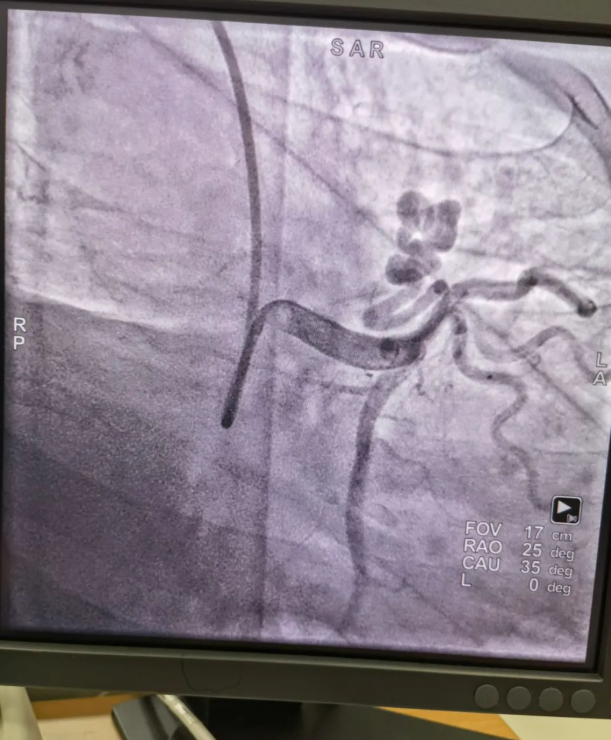

不久前,來(lái)自新疆的患者石先生去年至今反復(fù)胸悶、氣短、胸痛,就診于新疆某院,懷疑“冠心病”,住院行冠狀動(dòng)脈造影術(shù),石先生造影提示“冠狀動(dòng)脈肺動(dòng)脈瘺”,而他并非“冠心病”,所以給予的“冠心病”治療,效果不佳。出院后仍反復(fù)出現(xiàn)胸痛、胸悶、氣短等癥狀,經(jīng)親友介紹了解到西安國(guó)際醫(yī)學(xué)中心醫(yī)院心臟病醫(yī)院心臟內(nèi)科二病區(qū)曾廣偉主任,多年來(lái)潛心研究心臟病介入治療,成功主刀救治了許許多多高危復(fù)雜病例,尤其是在先心病及結(jié)構(gòu)性心臟病封堵,以及冠心病、心律失常射頻消融及起搏治療等方面積累了豐富的診療經(jīng)驗(yàn)。

此病例罕見(jiàn),在曾廣偉從醫(yī)18年生涯里曾碰到有2個(gè)印象深刻的病例,患者分別是53歲和66歲,當(dāng)時(shí)建議患者入院進(jìn)行動(dòng)脈瘺的封堵術(shù),但患者和家屬考慮到這個(gè)手術(shù)案例極少,風(fēng)險(xiǎn)也高,均未接受手術(shù)治療建議,只是能采取藥物保守治療,出院后隨訪得知患者癥狀緩解效果不佳,后來(lái)在隨訪中也與53歲患者失去了聯(lián)系,而66歲患者因冠狀動(dòng)脈肺動(dòng)脈瘺出現(xiàn)反復(fù)心衰,在當(dāng)?shù)蒯t(yī)院藥物治療,短短2年時(shí)間,患者因?yàn)閯?dòng)脈瘺未及時(shí)手術(shù)失去了生命。所以此次患者石先生到訪,曾廣偉主任在詳細(xì)掌握病例資料基礎(chǔ)上,果斷建議進(jìn)行動(dòng)脈瘺的封堵術(shù)治療,為了提高手術(shù)成功率和精準(zhǔn)度,曾廣偉主任搜集相關(guān)診療資料,反復(fù)推演論證,經(jīng)過(guò)相當(dāng)充足的準(zhǔn)備工作,于5月18日成功進(jìn)行了封堵手術(shù),完全堵上了瘺口。

冠狀動(dòng)脈瘺是指冠狀動(dòng)脈與心腔、冠狀靜脈、肺動(dòng)脈等的異常連接,是一種少見(jiàn)的先天性心臟病,發(fā)病率為1.3%。而冠狀動(dòng)脈肺動(dòng)脈瘺是冠狀動(dòng)脈與肺動(dòng)脈之間產(chǎn)生的一種血管性瘺口,導(dǎo)致冠狀動(dòng)脈里的血液流入肺動(dòng)脈里,使冠狀動(dòng)脈里血液流量減少,出現(xiàn)心肌供血不足,冠狀動(dòng)脈肺動(dòng)脈瘺會(huì)使患者出現(xiàn)胸部疼痛、胸悶、呼吸困難、頭暈、乏力等一系列癥狀,隨著疾病不斷進(jìn)展,可引發(fā)心功能的障礙和心肌缺血,肺動(dòng)脈會(huì)逐漸形成肺動(dòng)脈高壓,還可能導(dǎo)致動(dòng)脈瘤的破裂,甚至威脅病人的生命安全,所以早期發(fā)現(xiàn)和治療冠狀動(dòng)脈肺動(dòng)脈瘺,對(duì)病人的預(yù)后改善具有重要的意義。